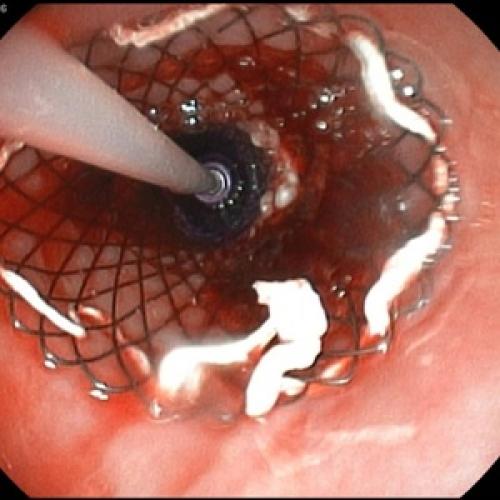

Хирургическое лечение хронического панкреатита

Когда заболевание запущено, а препараты для терапии хронического панкреатита уже не оказывают должного действия, применяются инвазивные методы лечения, в том числе оперативное вмешательство. Хирургическим путем удаляют орган целиком или его наиболее пораженные части, после чего обязательно применение ферментных препаратов, возмещающих гипофункцию поджелудочной железы. Показаниями к операции выступают:

- Полное разрушение ткани органа,

- Наличие опухолевых образований, некроза,

- Появление фиброза и свищей,

- Закупорка протоков камнями.